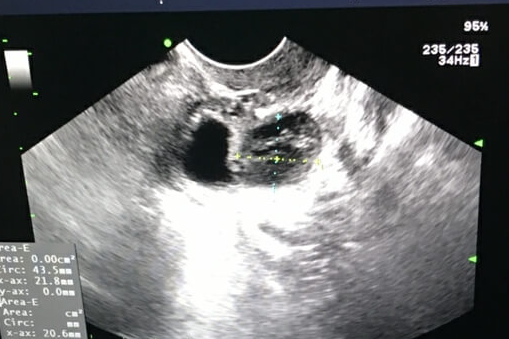

逸夫医院生殖中心成立于1998年。医院第三代试管成功率较高,新鲜移植周期的临床妊娠率保持在45%左右,冷冻融化胚胎移植周期的临床妊娠率保持在50%左右。目前,辅助生殖项目包括试管婴儿(即体外授精-胚胎移植、IVF-ET)、卵细胞浆中的单精子显微注射(ICSI)、夫精人工授精(AIH)、冷冻保存。囊胚培养和冷冻保存、经皮附睾或睾丸精子抽吸+单精子卵胞浆注射、胚胎辅助孵化(AH)、阴道减胎。